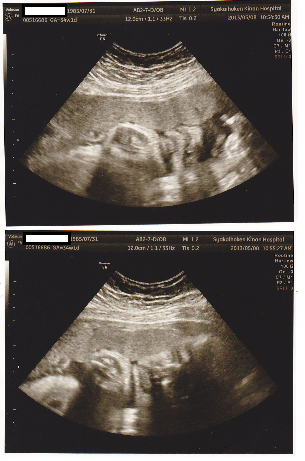

エコーも隅々まで教えてくれて、お顔のエコーの写真をもらえました(^^)

今のところ、主人そっくり・・・・(笑)

大きさも 2275g 順調☆